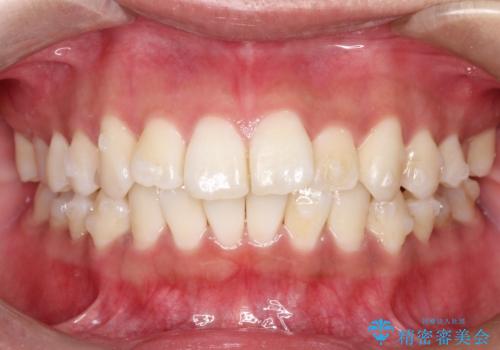

がたがたをインビザラインで整った歯並びへ

- 全体的ながたつきを主訴に来院されました。

抜歯矯正も考えられる状態でしたが、患者様が非抜歯での矯正を希望されたため、歯と歯の間をわずかに削りスペースを作り、全体を整える計画としました。

非常に協力的な患者様でしたので、スムーズに治療を終えることができました。